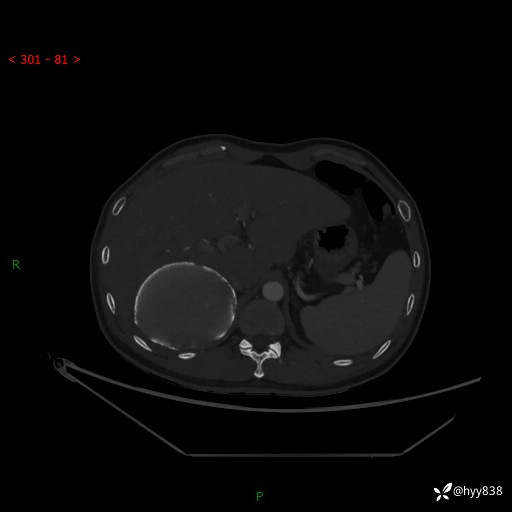

性别:男

年龄:50岁

简要病史:夜尿增多半月,发现肾功能异常1天,超声发现腹膜后占位

腹部CT平扫+增强